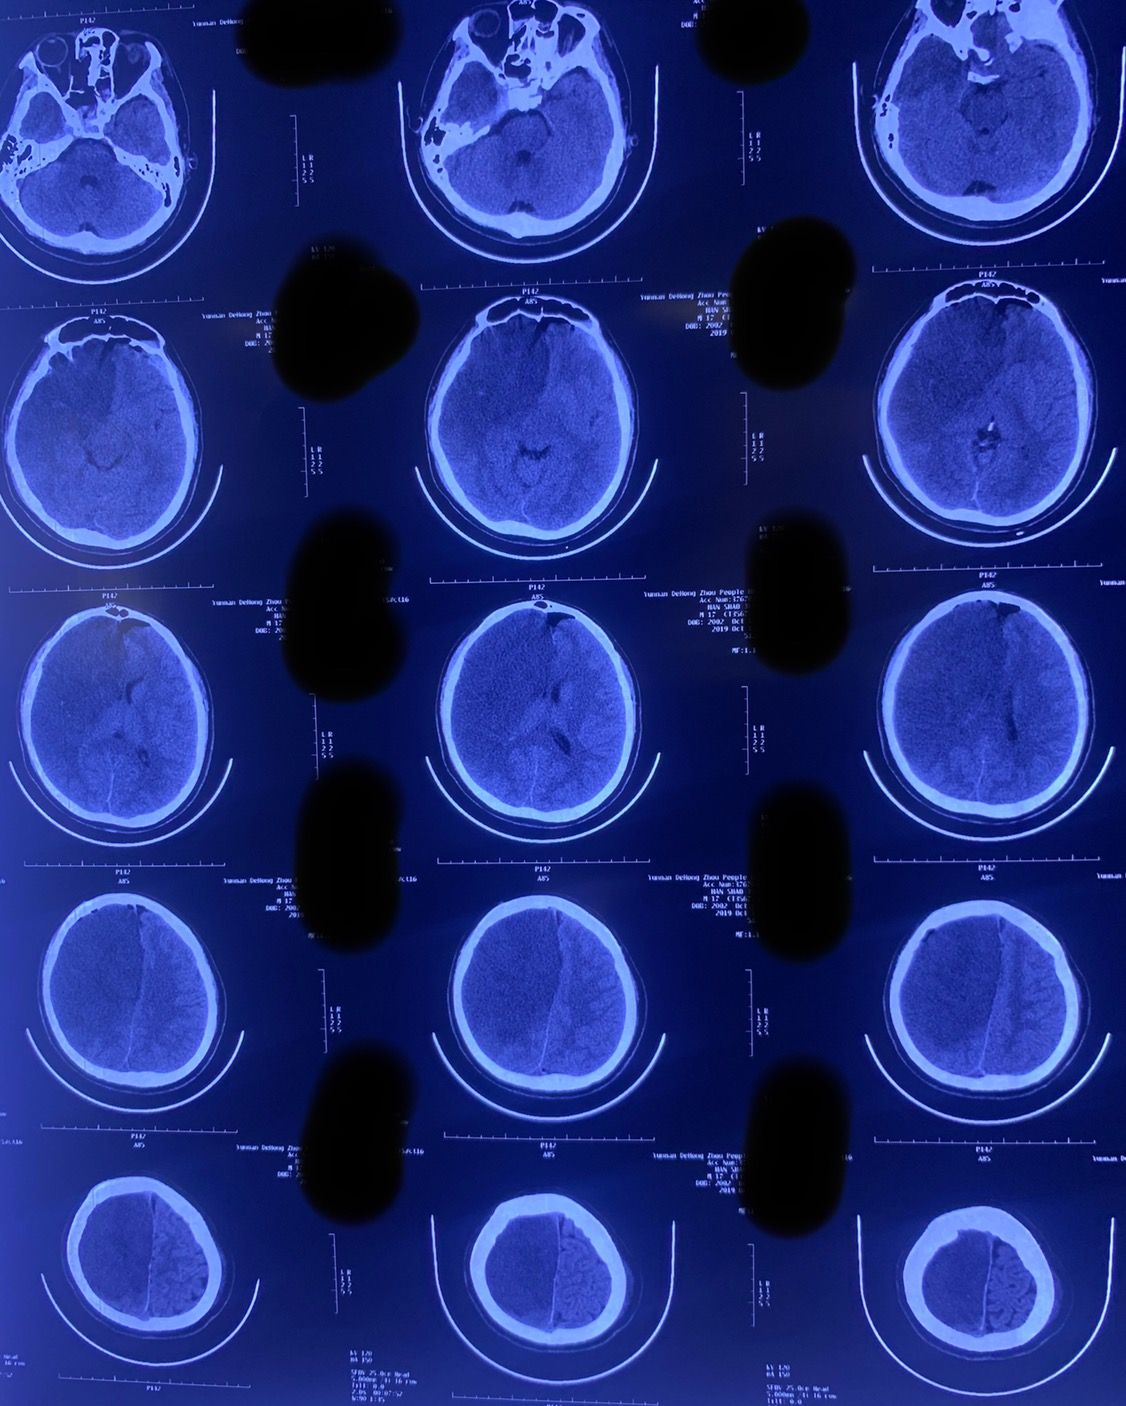

再次手术后于10月18日复查CT

10月24日再次复查头颅CT:中线回移,脑室系统逐渐显示。此时骨窗压力亦明显下降。